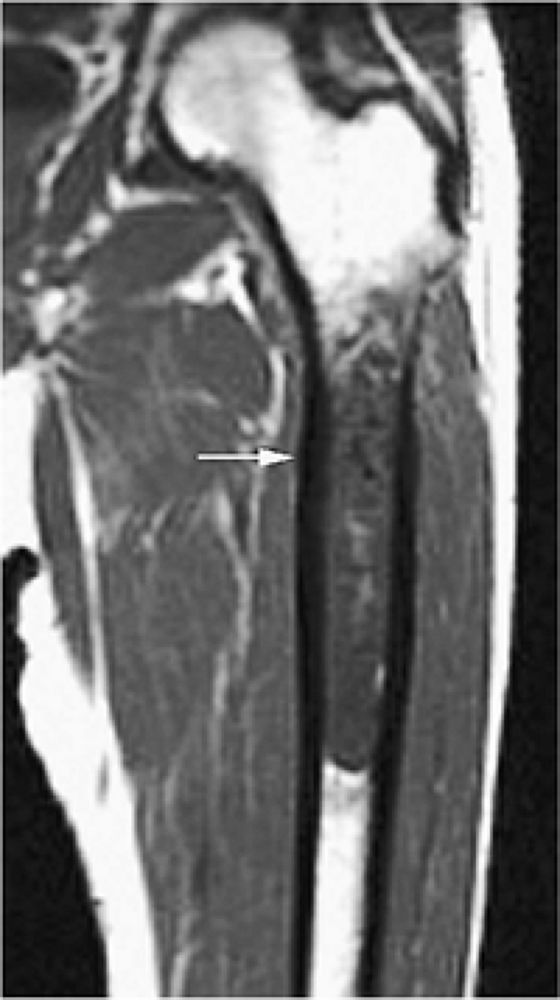

FIGURE 14-3 ● Chondrosarcoma of the proximal femoral shaft is seen on a coronal T1-weighted image. Cortical thickening (arrow) demonstrates low signal intensity on the T1-weighted image.